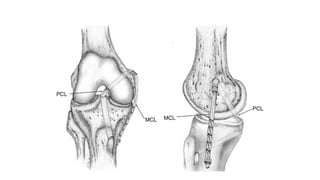

POSTERIOR CRUCIATE LIGAMENT

• 5-20% of all knee ligamentous

injuries

• PCL is the primary restraint to

posterior tibial translation

• functions to prevent

hyperflexion/sliding

• 38 mm in length x 13 mm in

diameter

• strength is 2500 to 3000 N

MEDIAL COLLATERAL LIGAMENT

• Excessive valgus stress on the knee

• Often an isolated injury

• Can be managed nonoperatively in the majority of patients

• Most common ligamentous injury (40% knee ligamental injuries)